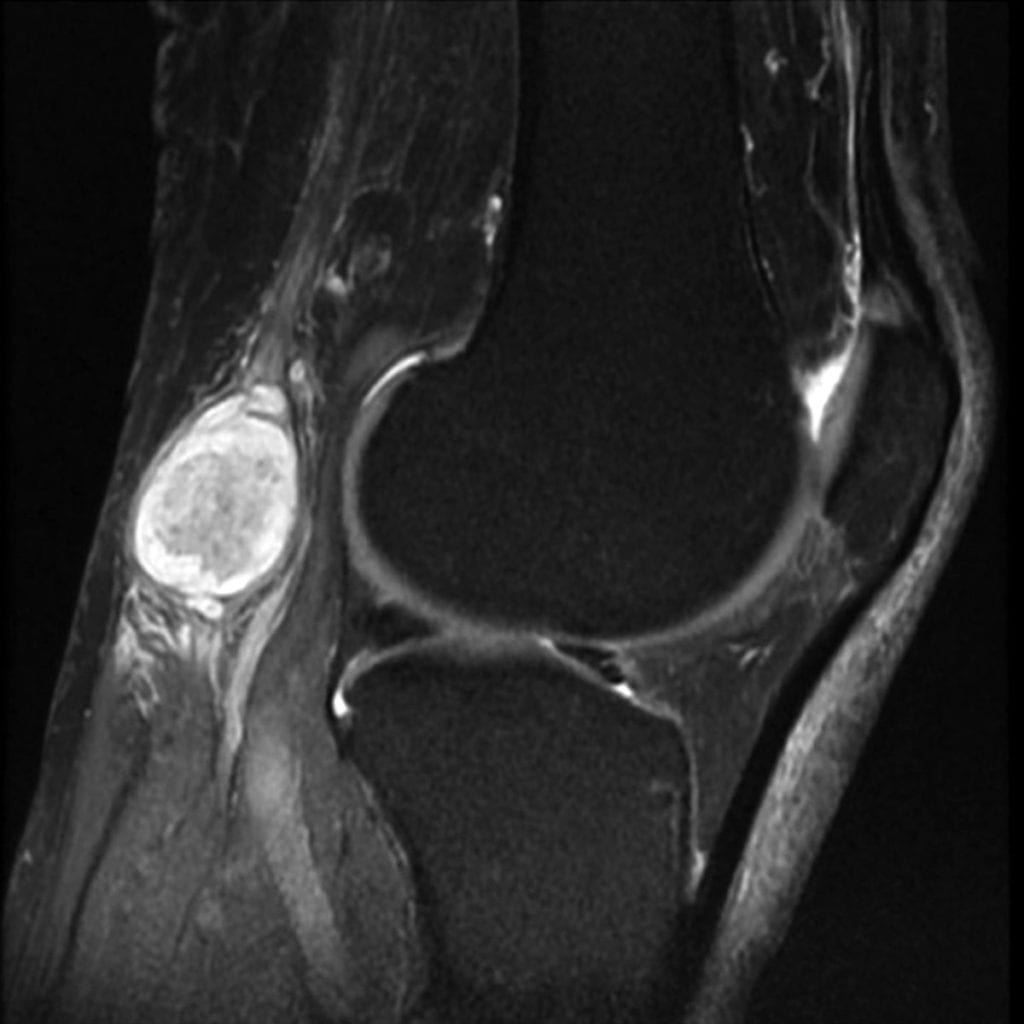

- синовиальная киста проявляется при высоком выбросе организмом некой синовиальной жидкости. Обуславливается выпиранием в подколенной области, а сам мешочек со временем увеличивается в объеме. Истинная причина проявления этого образования неясна, но чаще всего этим заболеванием подвержены люди, имеющие диагноз — ревматоидный артрит. Поскольку консервативные способы терапии дают низкий эффект, врачи выбирают оперативное вмешательство. Медицина сегодняшнего времени предлагает множество вариантов избавления от проблемы, одно из них называется эндоскопическим удалением новообразования;